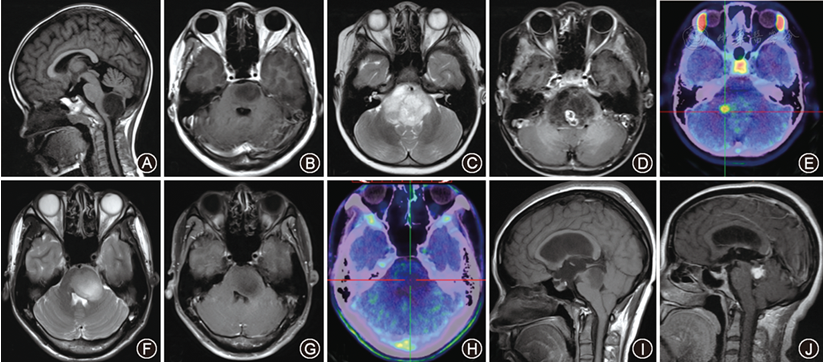

现代医学技术的进步提供了多种降低并发症的方法。首先,外科医生、麻醉医生、护理人员等凭借丰富的临床经验,能够预判术中可能出现的并发症并采取预防措施。其次,多项技术和设备有助于降低手术风险,例如术中唤醒技术可通过患儿与医生的实时互动来监测语言等重要脑功能。此外,术中电生理监测、术中超声、神经导航、术中成像及术中磁共振等设备也为安全手术提供了重要保障。

德国INI术中磁共振复合手术室